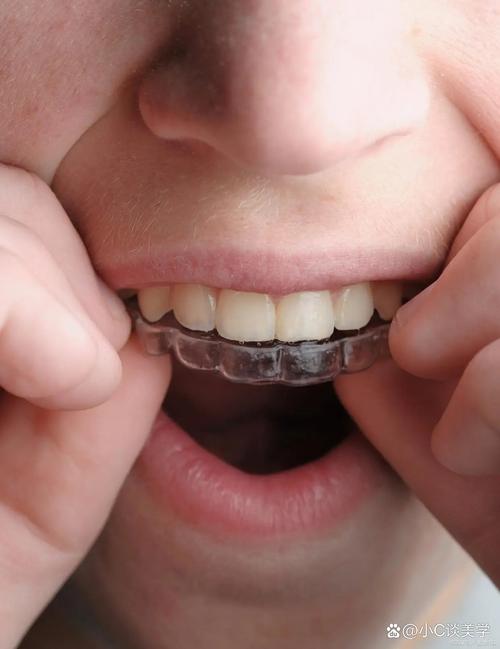

修复完成后并非治疗结束,需长期保持:正畸后佩戴保持器(如 Hawley 保持器、透明保持器)至少1年,防止牙齿复发移位;修复体需定期检查(每6个月1次),注意口腔卫生,避免咬硬物,种植牙还需每年进行专业洁治。